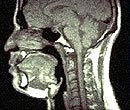

Airway

Closure During Sleep - Apneic

Apneic

Patient (Mid- Sagittal Section)

Normal

Subject (Mid - Segmental Section)

Soft

Tissue Comparison of an Apneic and a Normal